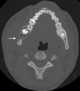

Unerupted tooth

Dentigerous cyst, also known as follicular cyst is an epithelial-lined developmental cyst formed by accumulation of fluid between the reduced enamel epithelium and crown of an unerupted tooth. It is formed when there is an alteration in the reduced enamel epithelium and encloses the crown of an unerupted tooth at the cemento-enamel junction. [Source: Wikipedia ]